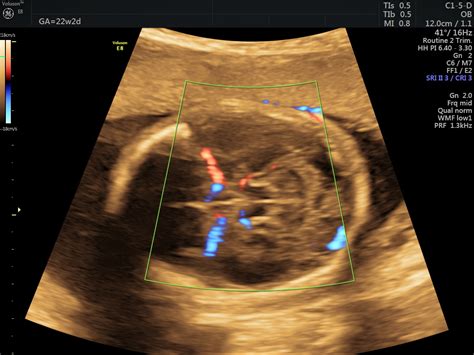

- Screening prenatal și diagnosticare ecografică antenatală performantă pentru depistarea malformațiilor fetale.

Spitalul oferă o abordare integrată, incluzând diagnosticare ecografică antenatală, îngrijire specializată în secția de terapie intensivă neonatală și posibilitatea efectuării intervențiilor chirurgicale necesare în primele zile de viață ale bebelușului.